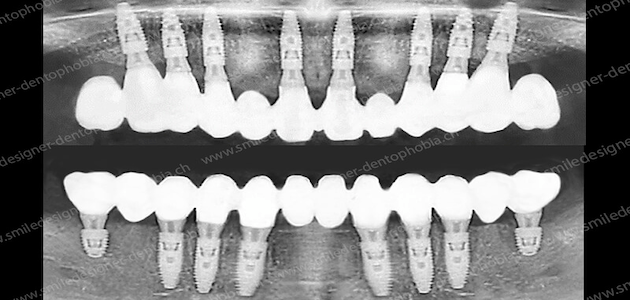

Implantologie avancée, chirurgie orale, greffes complexes : notre savoir-faire reconnu internationalement permet de traiter même les cas les plus exigeants.

Grâce au flux numérique 3D complet, comme scanner dentaires 3D et caméra optique 3D, chaque projet est planifié scientifiquement et réalisé avec une précision chirurgicale, pour un sourire sur mesure en parfaite harmonie avec vos traits du visage.

Le Dr Jérôme Weinman et son équipe réalisent des réhabilitations implantaires complètes en une seule séance sous sédation contrôlée, dans un cadre médical exclusif.

LA POSE DE VOS IMPLANTS DENTAIRES EN 1 SHOT

REMPLACEZ VOS DENTS MALADES GRÂCE AUX PROTOCOLES DE POSE D'IMPLANTS AVEC MISE EN ESTHÉTIQUE IMMÉDIATE